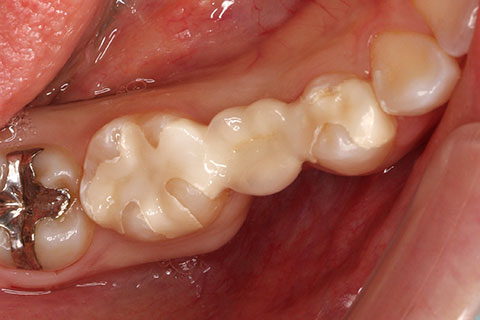

• ジルコニアブリッジの症例3

治療前

治療後

年齢・性別

25歳女性

治療期間

1ヶ月

抜歯

右下5番欠損

治療費

16.5万円(税込み)

備考

歯質の削除量を最小限に抑えるブリッジ治療

治療内容

欠損部位の隣接歯を削合後、セメント合着

施術の副作用(リスク)

知覚過敏、歯髄炎、荷重負担